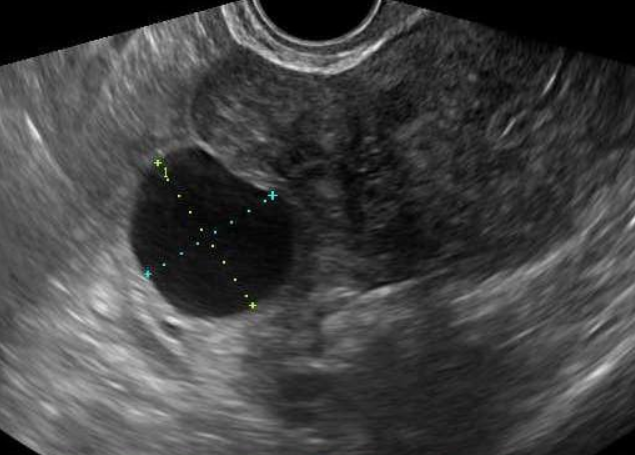

자궁·난소 등의 이상 소견을 확인하는 여성생식기 초음파 검사는 여성에서 흔히 발생하는 질환인 자궁근종, 난소 낭종 등을 진단하기 위한 기본적인 검사방법임에도 불구하고 그간 4대 중증질환(암·심장·뇌혈관·희귀난치)에 한해 제한적으로 건강보험이 적용됐었다.

여성생식기 초음파 검사의 보험적용 범위는 의사의 판단 하에 자궁, 난소, 난관 등에 질환이 있거나 질환을 의심하는 증상이 발생하여 의학적으로 검사가 필요한 경우까지로 확대된다.